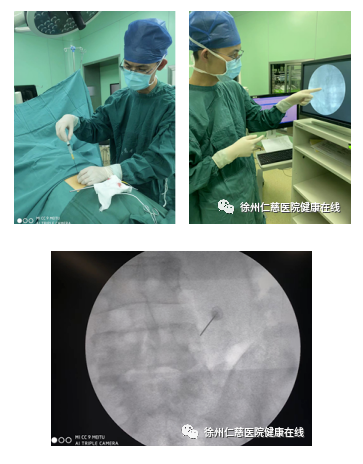

陈先生入院第2天,秦小虎主任为其实施了“腰4-5双侧脊神经后支射频热凝术”。术后观察24小时后王先生感到腰部疼痛缓解,出院后随访,症状也未再复发。

射频热凝技术操作15-20分钟便可完成整个手术,术后有些患者几个小时就可以出院了。以往要开刀、全麻,近十几公分的创口,血肉模糊的场景都看不到了。